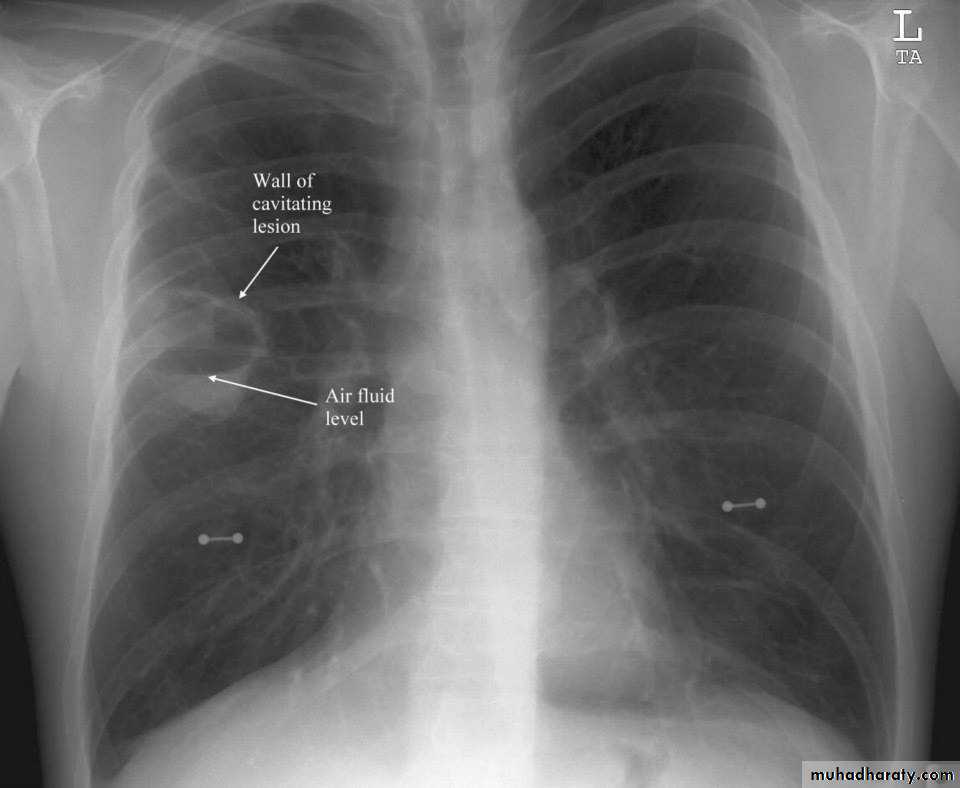

Cavity ( air containing lesion )

Thin walled <3mm

Thick walled >3mm

Cavity with air fluid level

Air fluid level with membrane (ruptured hydatid cyst )